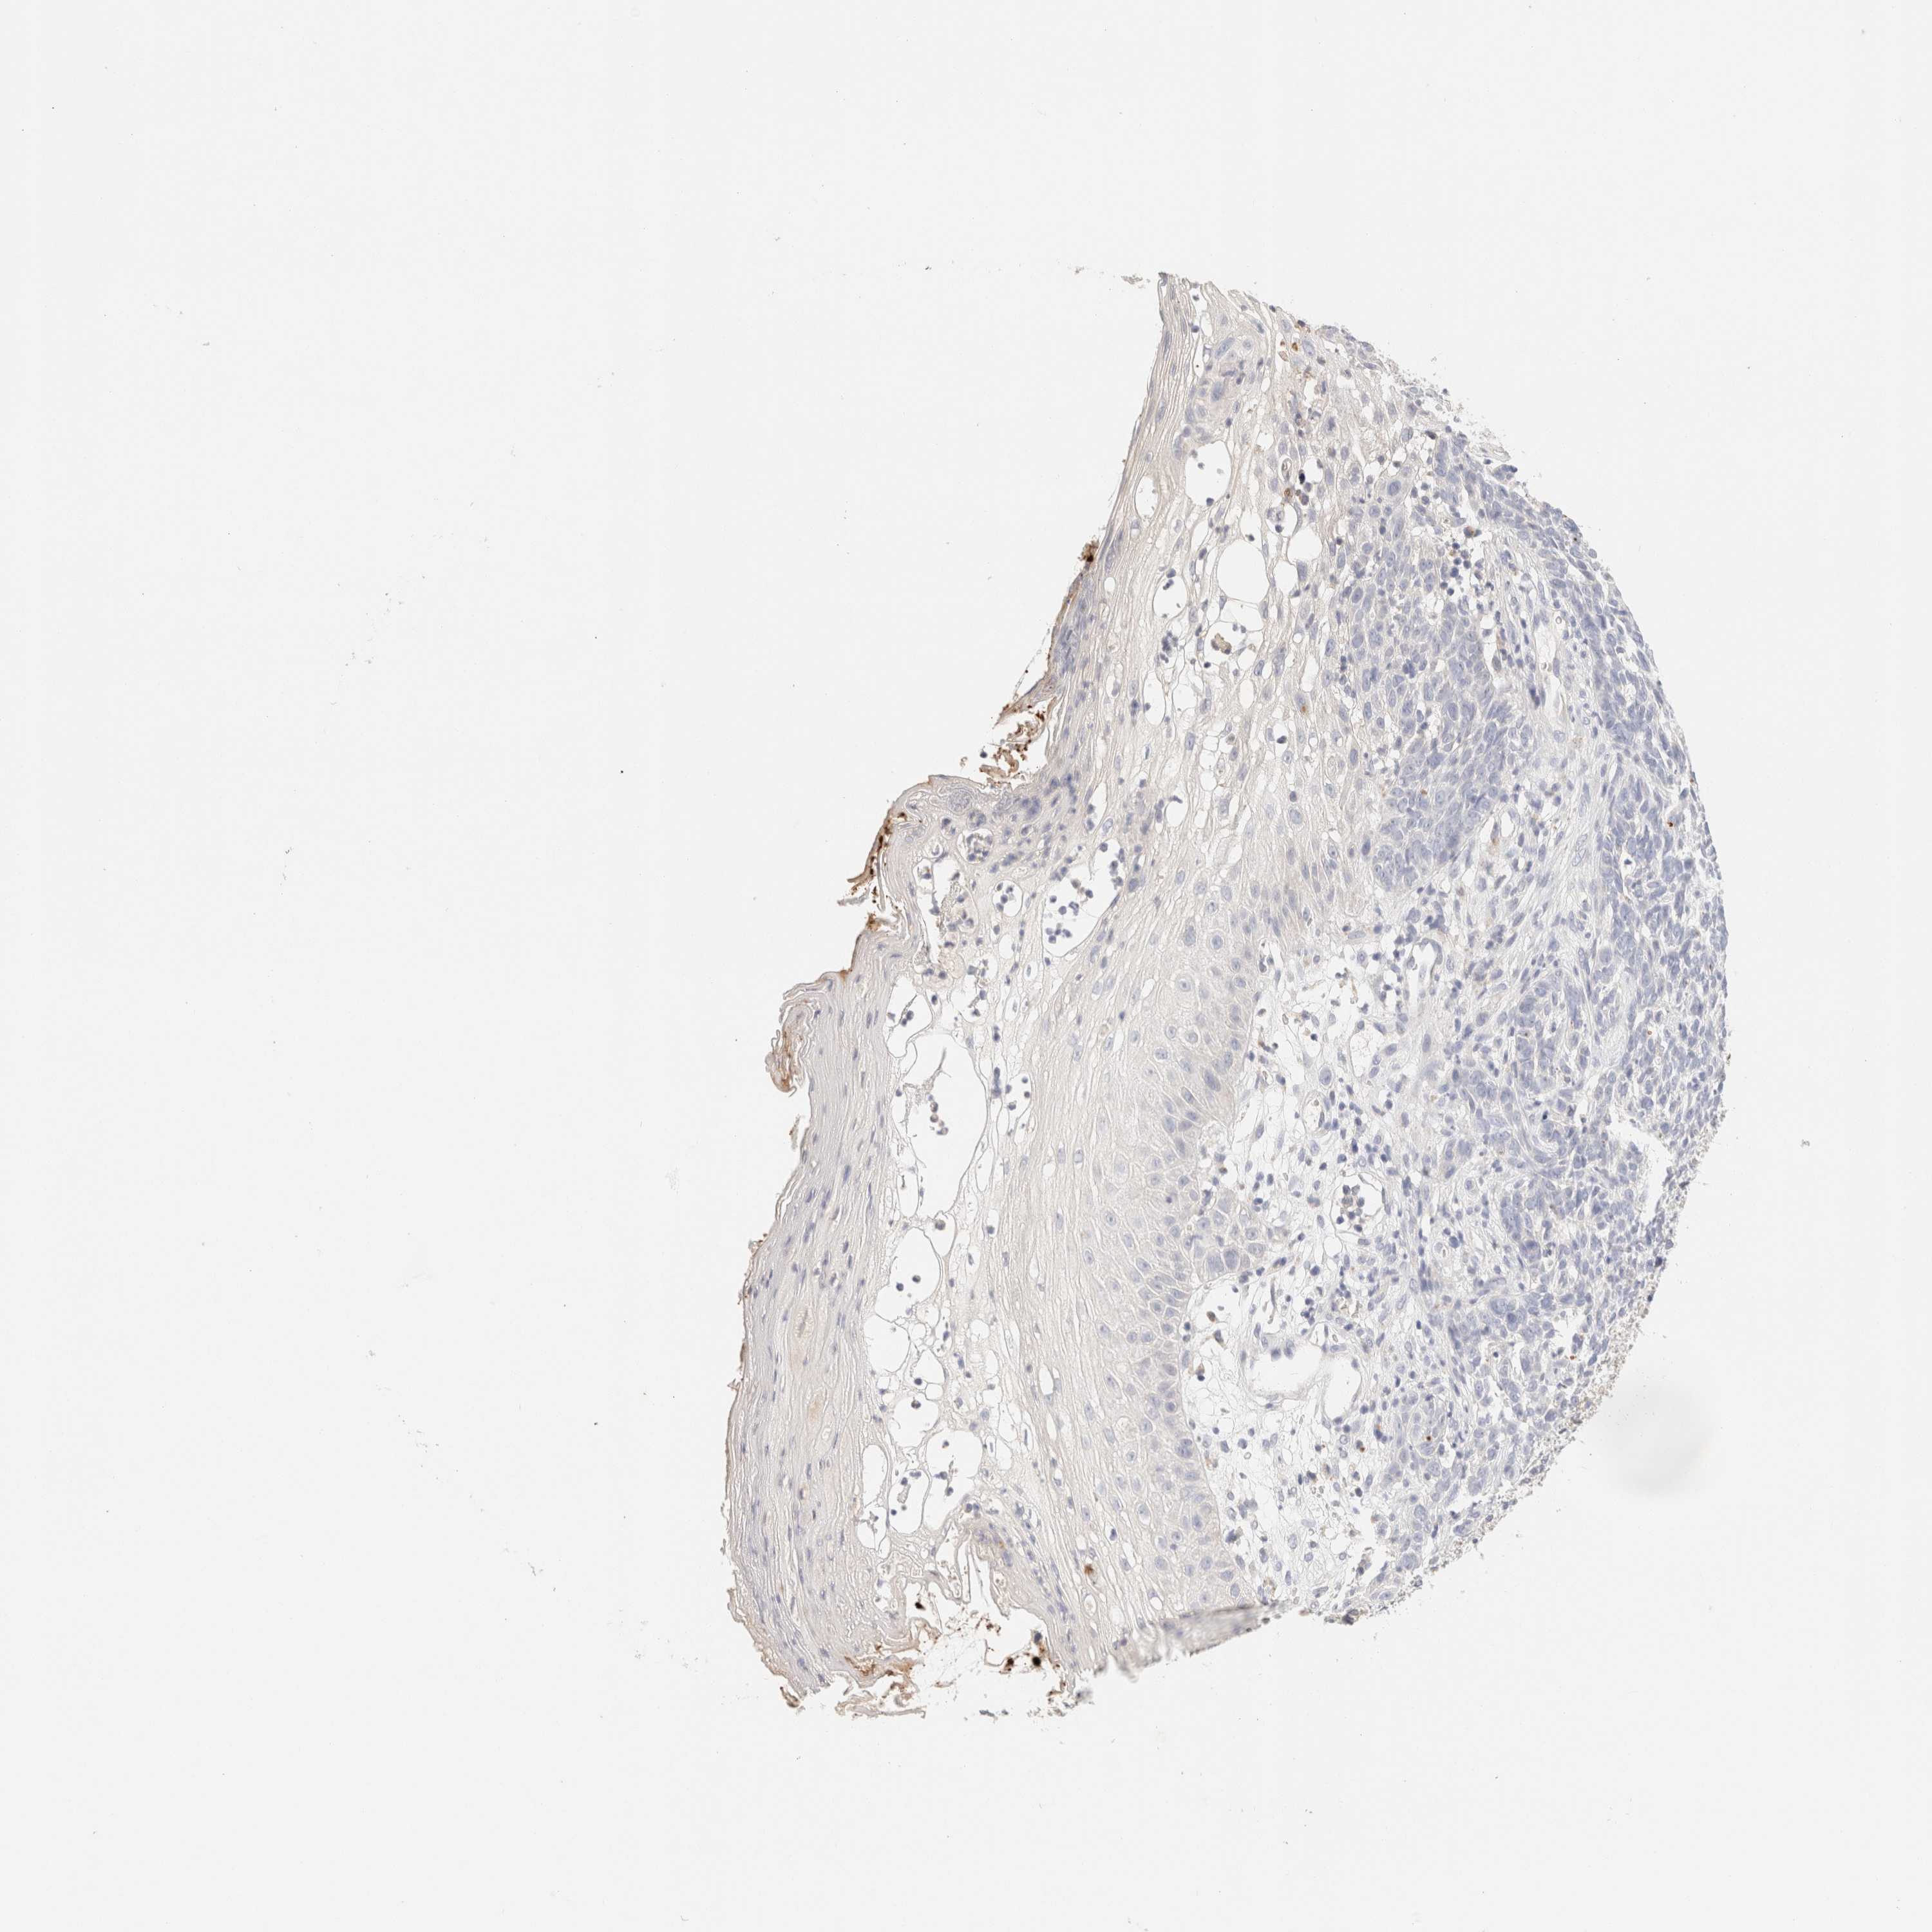

Basal cell and squamous cell cancer

SKIN CANCER - Protein expressioni

A mouse-over function shows sample information and annotation data. Click on an image to view it in a full screen mode. Samples can be filtered based on level of antibody staining by selecting one or several of the following categories: high, medium, low and not detected. The assay and annotation is described here.

Each image is clickable and will lead to virtual microscopy that enables deeper exploration of all samples and also displays staining intensity scores, fraction scores and subcellular localization as well as patient and tissue information for each sample.

Antibody CAB026270

Staining

High

Medium

Low

Not detected

Intensity

Strong

Moderate

Weak

Negative

Quantity

>75%

75%-25%

<25%

None

Location

Nuclear

Cytoplasmic/membranous

Cytoplasmic/membranous,nuclear

Basal cell carcinoma